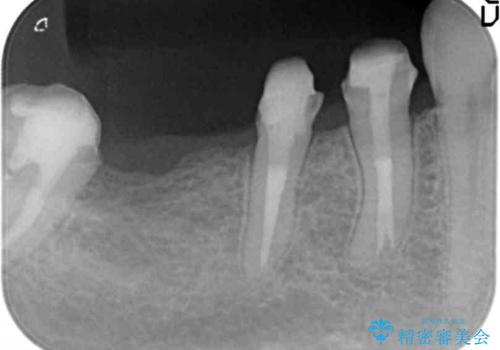

臼歯部メタルフリー再補綴

クラウン・ブリッジを作り替えるにあたり虫歯の徹底的な除去・根管治療のやり直しを行い今後やり直しをしなくて済むような環境を整えていきます。

装着して長期間経過したブリッジやクラウンは隙間から細菌が侵入し虫歯が再発してしまっていることがあります。

長期的に問題のないブリッジ・クラウンを作製するため、虫歯をしっかりと除去すること精密な根管治療を行うことが肝要です。